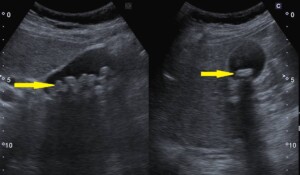

@腹部エコーにて発見された胆石